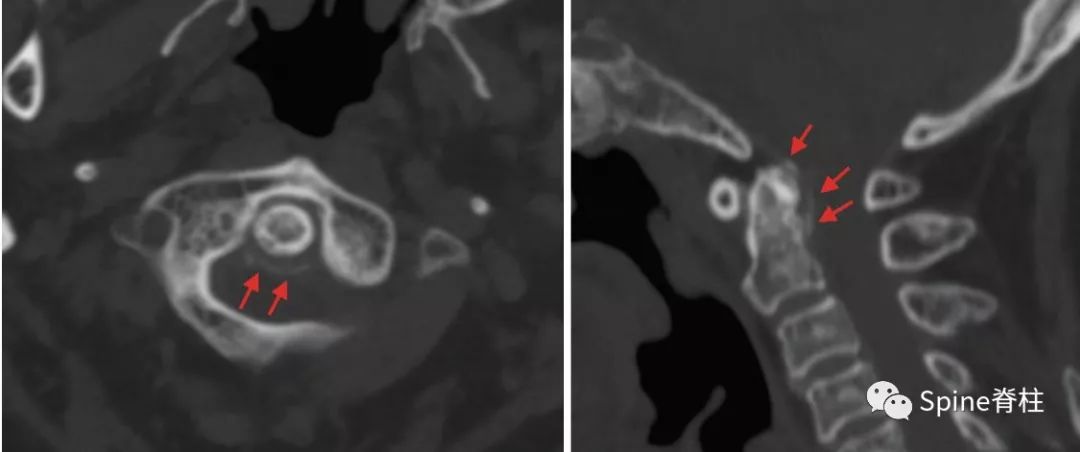

齿状突加冠综合征(Crowned dens syndrome)是指患者以急性颈痛伴随颈椎活动受限就诊,常伴发热,且影像学上表现为齿状突上方或周围出现大小不一、高密度、不规则的钙沉积影,但主要发生在齿状突后侧。因影像学征象犹如齿突戴上了一顶皇冠(如下图),因而得名齿状突加冠综合征,是因钙盐晶体在枢椎齿突周围软组织中沉积形成的。早在1985年,Bouvet等 (Arthritis Rheum, 1985) 首先报道此病。

颈椎CT冠状位重建显示犹如齿突戴上了一顶皇冠故得名齿状突加冠综合征

患者女,76岁。无明显诱因下出现颈部疼痛、僵硬伴发热 3 d 入院 ,颈部疼痛呈间歇性,颈痛视觉模拟评分(VAS)为7分,体温37.7~38.8℃,无四肢疼痛麻木,无行走不稳,二便正常。既往无痛风、类风湿关节炎病史。入院体检:颈椎旋转明显受限,颈部肌肉僵硬,未查及明显神经或脊髓损伤体征。实验室检查:白细胞11.2×109/L,红细胞沉降率35.4 mm/h,超敏C反应蛋白14.7 mg/L,类风湿因子及降钙素原正常。颈椎CT平扫示齿状突后侧寰椎横韧带弧形钙化(左图箭头)和竖直线样钙化(右图箭头)。依据患者病史、体征及辅助检查,齿状突加冠综合征可基本诊断。入院后给予氯诺昔康 8 mg静脉滴注每日2次,地塞米松起始量10 mg静脉滴注每日1次,3日后改为5mg/d。连续治疗5 d后,患者入院时症状明显缓解,复查白细胞、红细胞沉降率、超敏C反应蛋白均恢复正常。随访半年,未有颈痛伴发热症状出现。